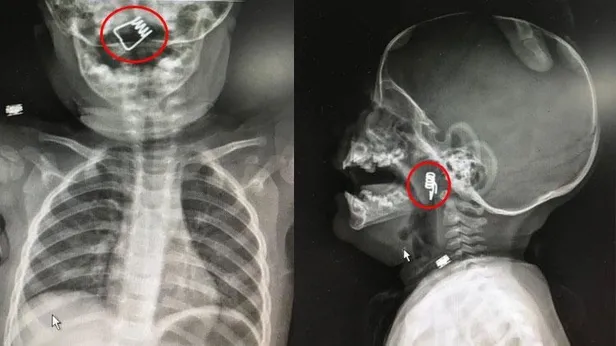

Nevşehir Devlet Hastanesi Acil Polikliniği'ne getirilen bebeği, Acil Nöbetçi doktoru Mustafa Alpaslan muayene ederek gerekli tetkikleri yaptı. Çekilen röntgen filmlerinde mandal yayının lokalizasyonu ve durumu belirlendi. Daha sonra, KBB Uzmanı Op. Dr. Ahmet Cevatzade tarafından yapılan başarılı ameliyat sonucunda bebeğin genzine saplanan mandal yayı çıkartıldı.